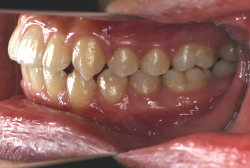

「出っ歯を治したい」という主訴で来院したケースです。診断の結果、「2級1類の上顎前突+軽度叢生」と判明しました。2級というのは、基本的に出っ歯の噛み合わせになっていることを言います。その中でも上の前歯が著しく外に反っているケースを、「1類」といいます。初診時の横向きの写真を見ると、それがはっきり分かります。上の前歯に押されて唇も膨らんで、審美線をかなりオーバーしています(審美線とは、鼻の先端と顎の先端を結ぶ線のことで、この線よりも唇は内側にある方が良いとされています)。

このような症状の場合は、前歯を内側に入れるためにかなり大量の隙間を必要とします。通常は上下左右の小臼歯を抜歯させていただくのが正解です。治療後は歯の角度が正しくなっただけでなく、唇の審美性が大幅に改善しました。もちろん噛み合わせ的にも正しい状態が確立しています。